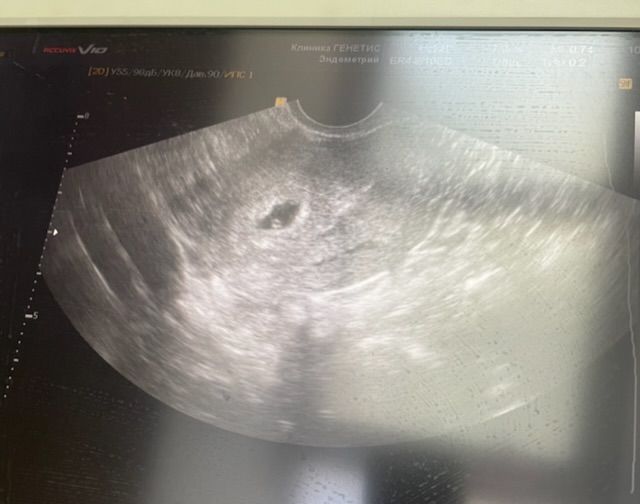

Разглядываем тесты // пока ждём результат ХГЧДевочки подскажите 18 ДПП сделали УЗИ врач сказала все хорошо, через недельку будем слушать сердечко. Но по картинке не могу понять что видно уже? Плодное яйцо, жм, эмбрион? Подскажите кто разбирается)

Плодное яйцо и желточный мешок точно вижу. Все хорошо у вас

Вот это овальное черное в центре (глазок)-это плодное яйцо , с белым ободком. В нем маленький кружочек пристеночно-это желточный мешок. Эмбриона пока не видно, появится в видимости чуть позже , чсс его тоже видно должно быть потом.

Яна Семёнова, мы с вами близко) у меня сегодня 17 дпп. Кровь была на 14 дпп 17672. На узи пойду 15ого числа. ПЯ и ЖМ у вас видно. Эмбриончик пока не вижу, но на 18 дпп узи рановато. Моя Ре сказала идти с 21 по 24 дпп